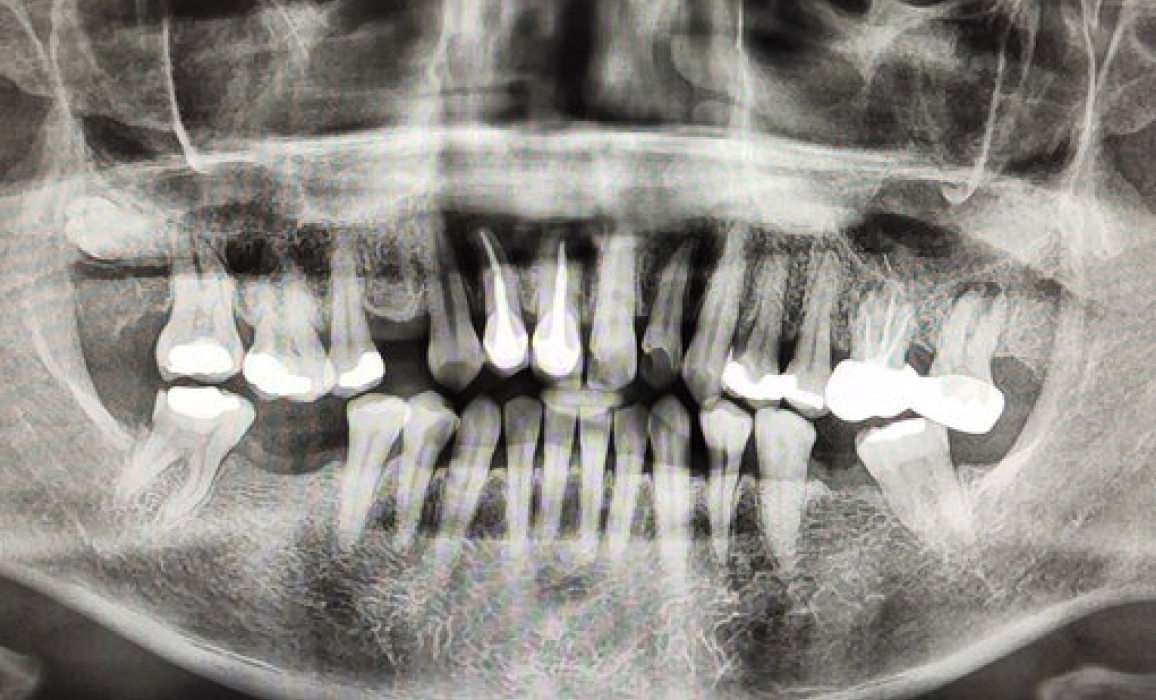

Advantages such as the simplicity of procedure, broadened scope of examination, less total radiation, eliciting information not possible through conventional intra-oral radiographs and above all comfort of patients need hardly any emphasis so far as OPG is concerned.

• For full mouth radiological examination of teeth and their supporting structures like the periodontium, bone etc.

• To detect impacted wisdom teeth, tumors, bone dysplasias,

• cysts or any other pathology in the facial region.

Showing all teeth along with surrounding bones, including T.M. joints in one film.